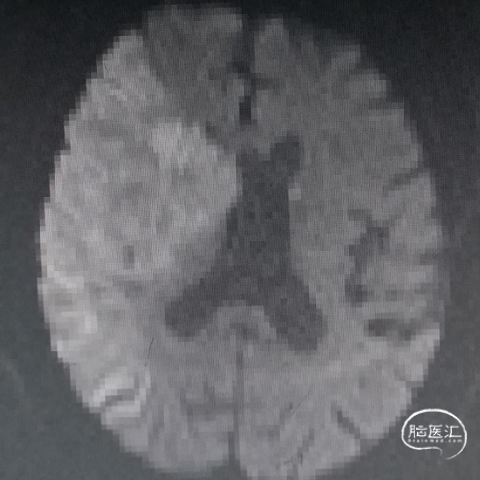

术后72h头颅MRI-DWI序列:右侧大脑中动脉供血区弥散受限,轻度脑回增宽、脑沟变浅;中线基本居中。